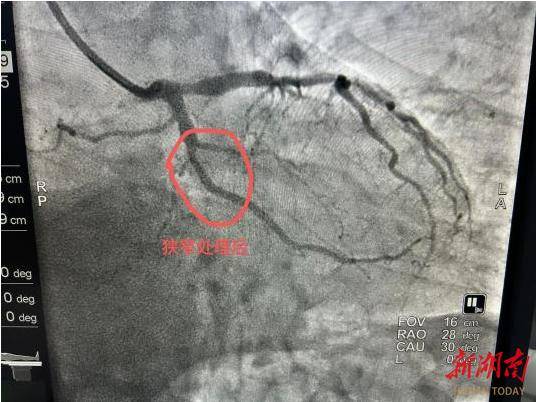

2. 适配特殊病变场景:像影像中这类局限性的血管狭窄,或是支架内再狭窄、小血管病变、分叉病变等情况,药物球囊能精准处理病变部位,避免了复杂病变下支架植入的局限性,也降低了多支架叠加的风险。

从影像看治疗效果:

“打通河道”且不留痕迹

此次治疗的造影对比极具说服力:术前狭窄处血管血流受阻,心肌供血不足,患者可能出现心绞痛等症状;药物球囊扩张后,狭窄处血管恢复正常管腔形态,血流顺畅通过,心肌缺血问题得到解决。更重要的是,血管内没有支架的“占位”,保留了血管的生理结构,为未来可能的再次治疗预留了更多空间。